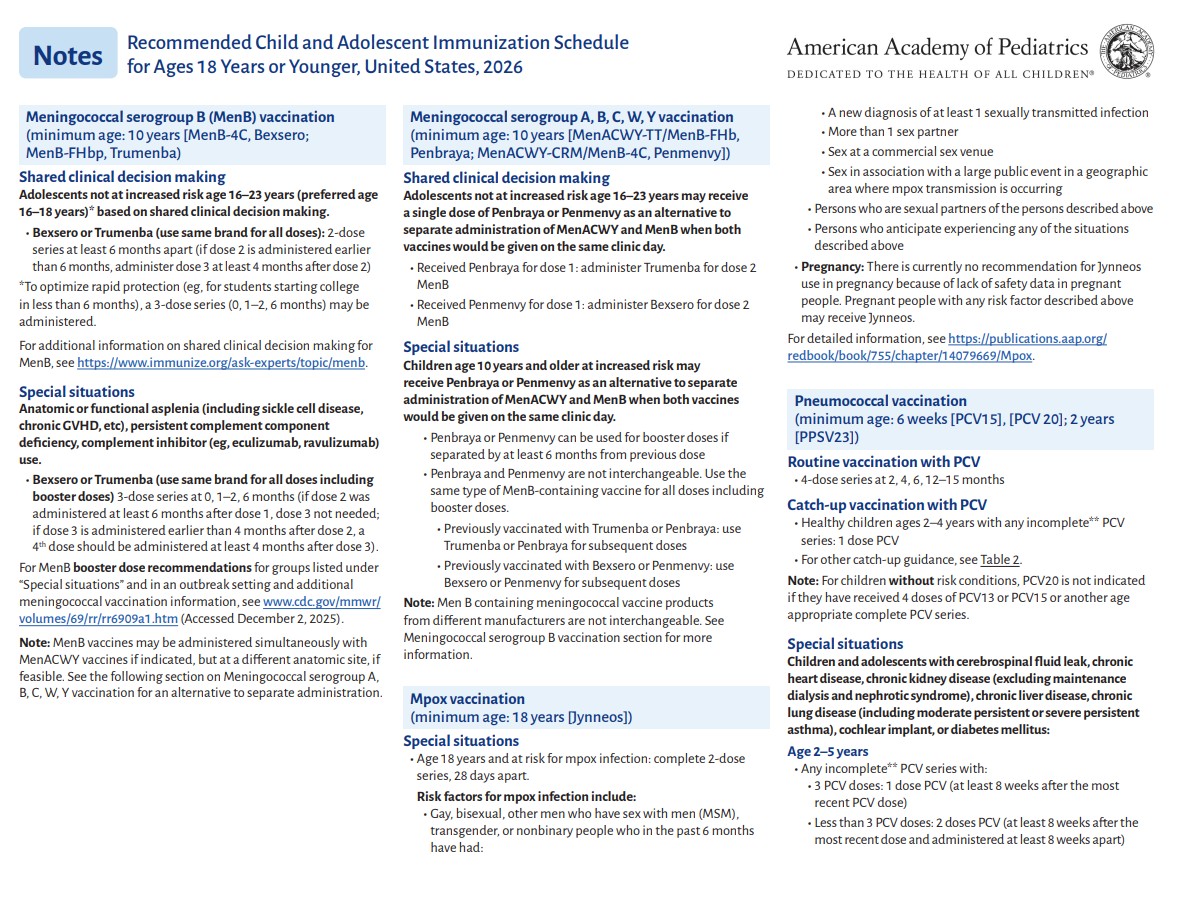

p 9

p 10

p 11

p 12